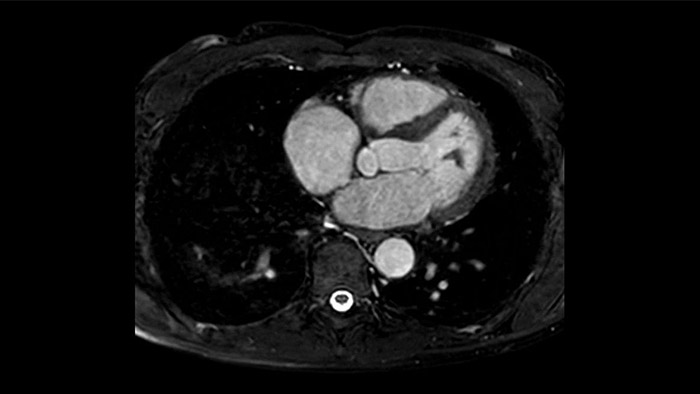

IntelliSpace Portal offers a Comprehensive Cardiac MRI Suite, providing dedicated workflows for functional analysis, viability, LGE, cardiac mapping assessment and RV/LV functional analysis in less than 5 min. per case1.

Diagnostic and prognostic utility of cardiac MR is increasing. Assess the anatomy and function of the heart using cine acquisitions, acquire information about perfusion and viability of the cardiac tissue, visualise potential edema with black blood sequence, access and even quantify tissue characterisation with CardiacQuant.